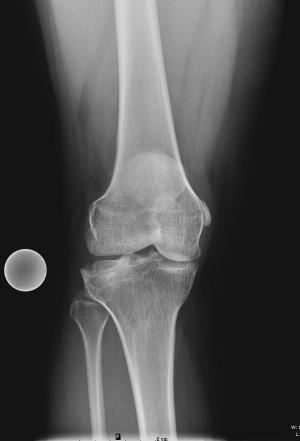

29-year-old female with history of remote right knee injury.